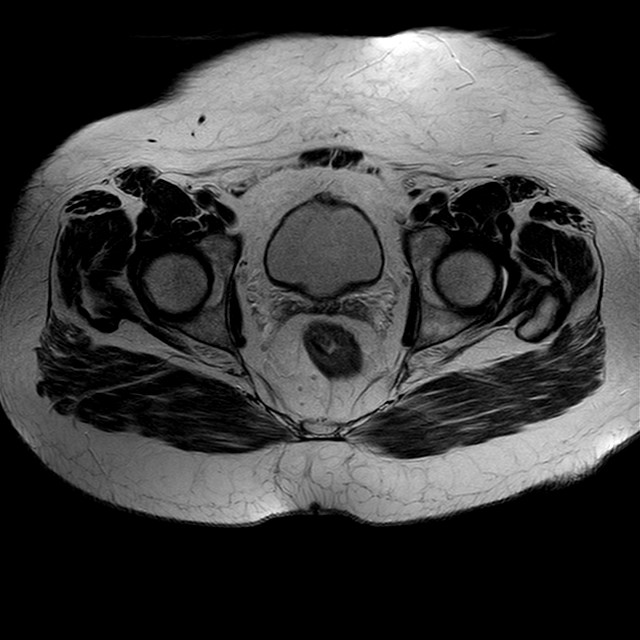

eT2w TSE

Evidenti e simmetriche alterazioni osteofitosiche in regione coxo femorale con riduzione delle rime articolari. Degenerazione completa del cercine glenoideo. Non attuali segni di versamento articolare. Non segni di edema osseo che escludono attuale algodistrofia od osteonecrosi. Lieve e simmetrica riduzione del trofismo della muscolatura glutea.